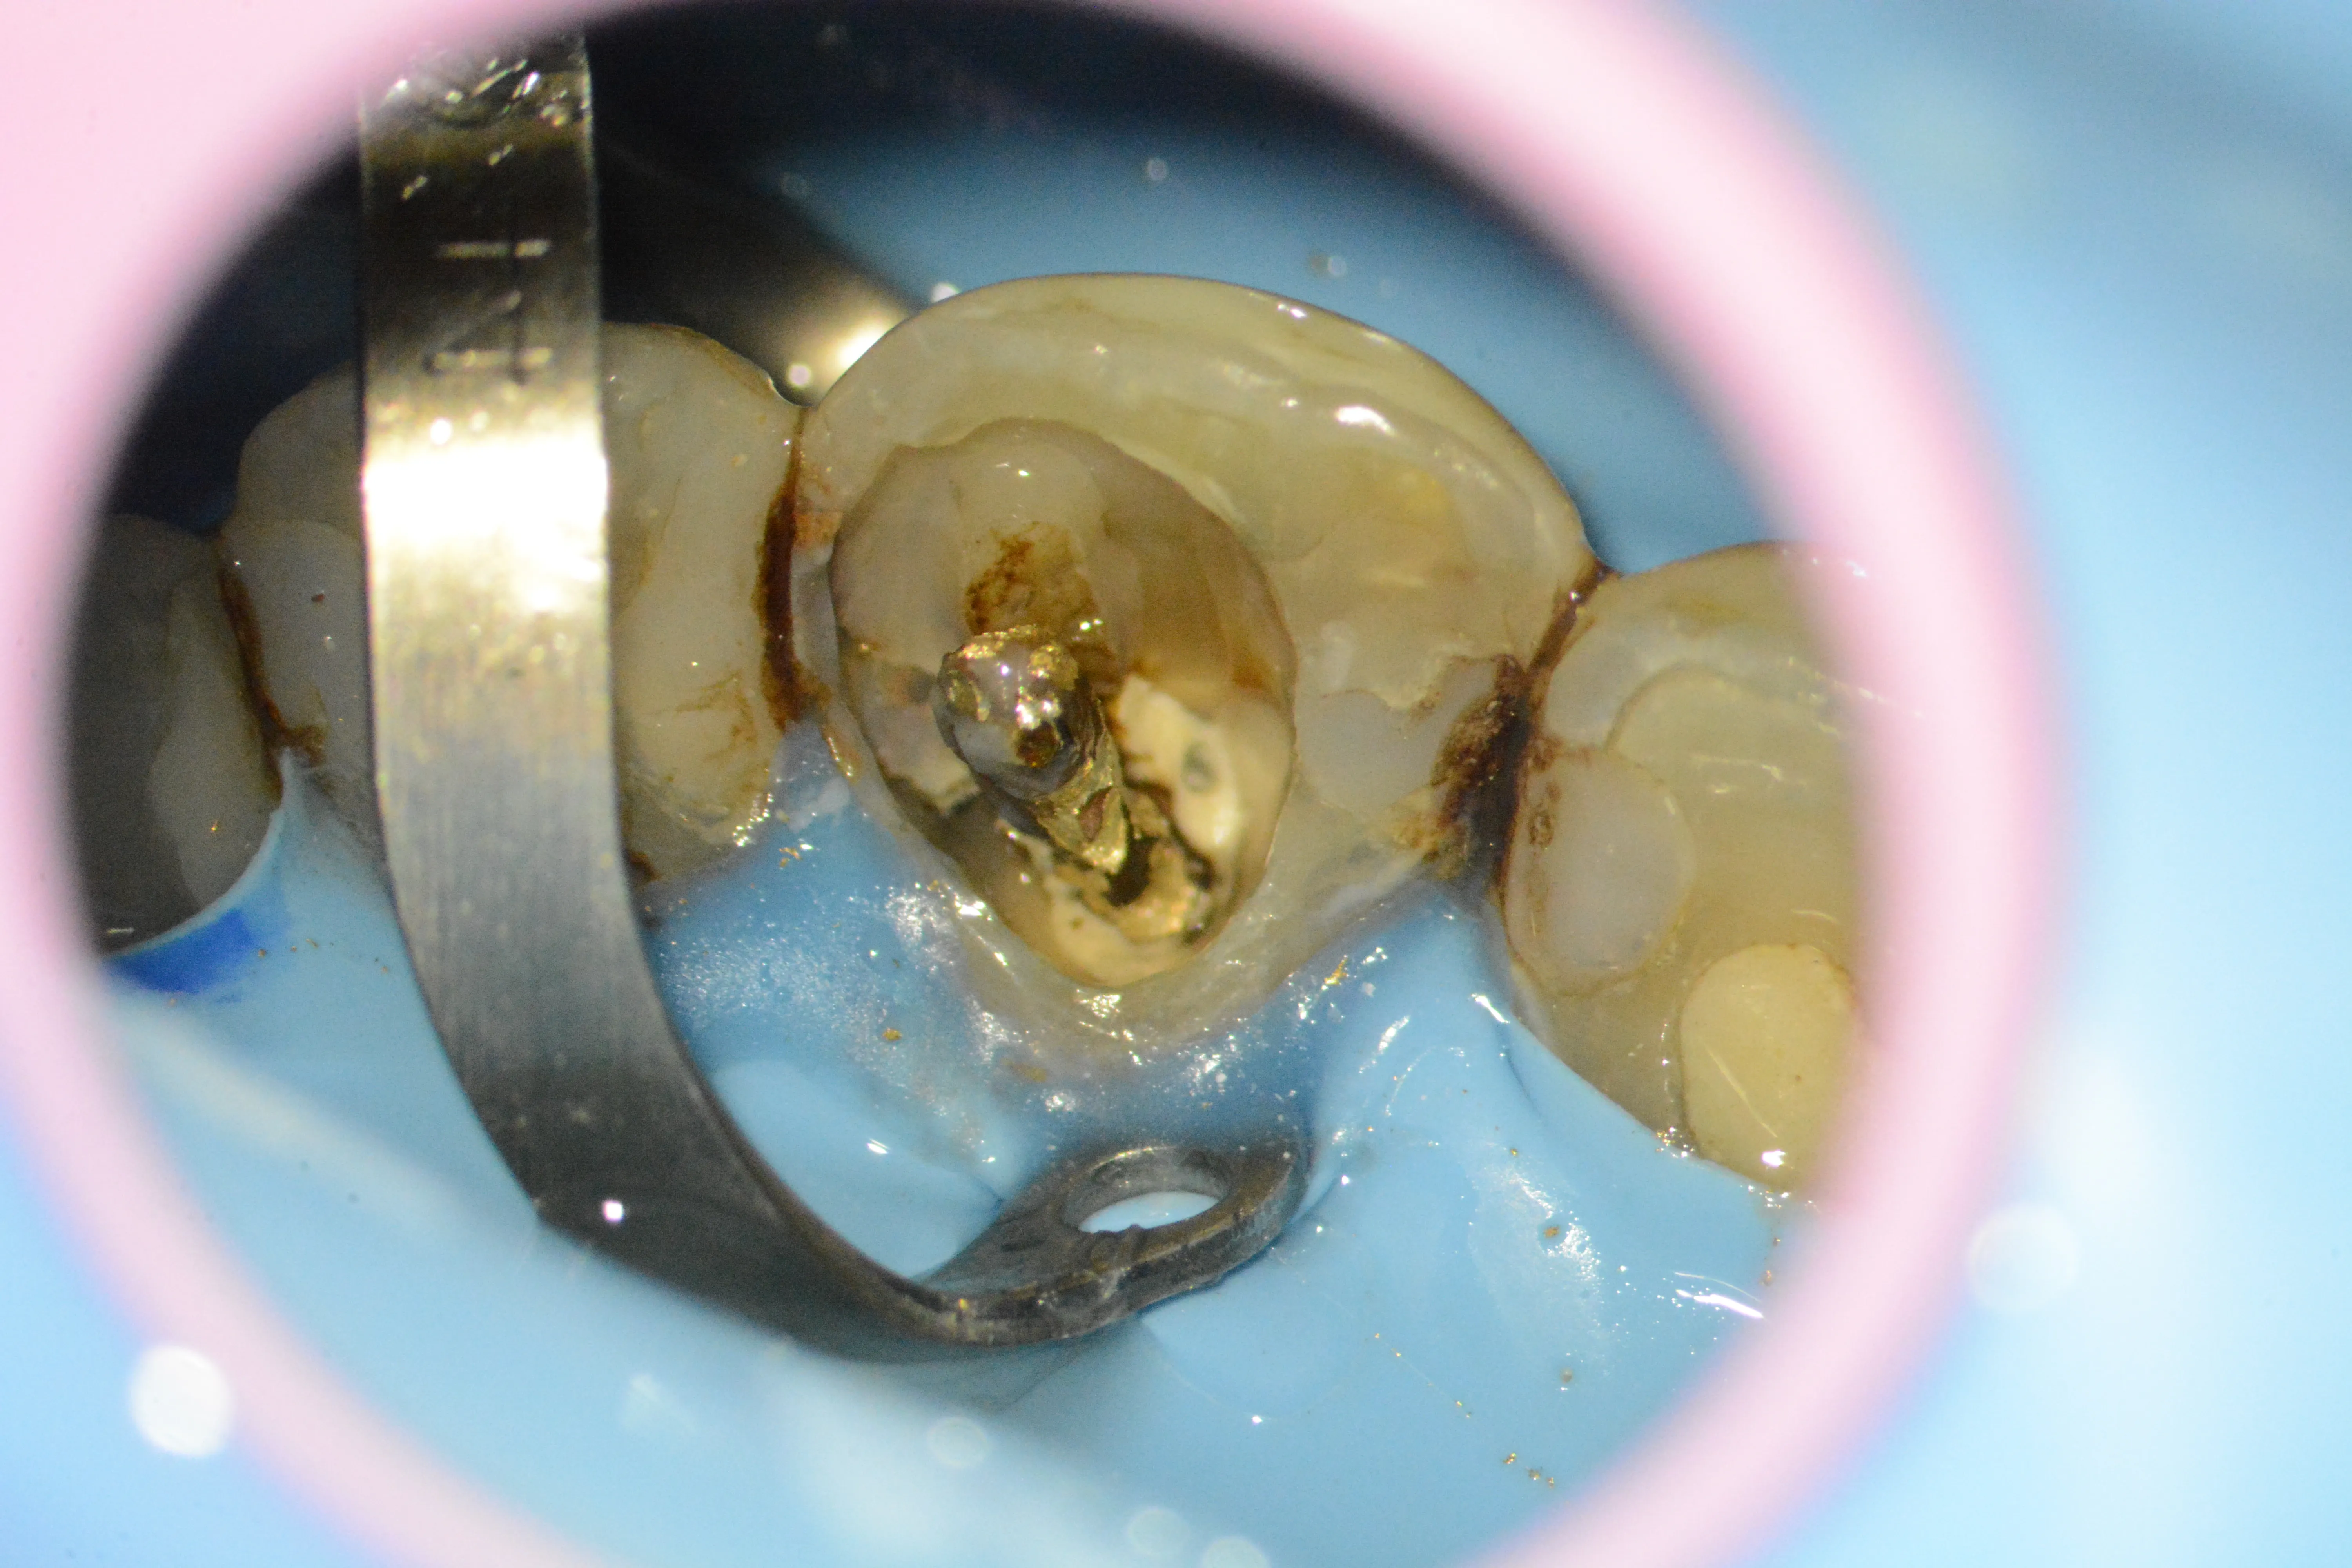

3 – Aspectul pivotului metalic după eliberarea din partea coronară și resturi de ciment cu carie secundară

4 – Aspectul pivotului metalic dislocat

5 – Prezența unei perforații la nivel cervical